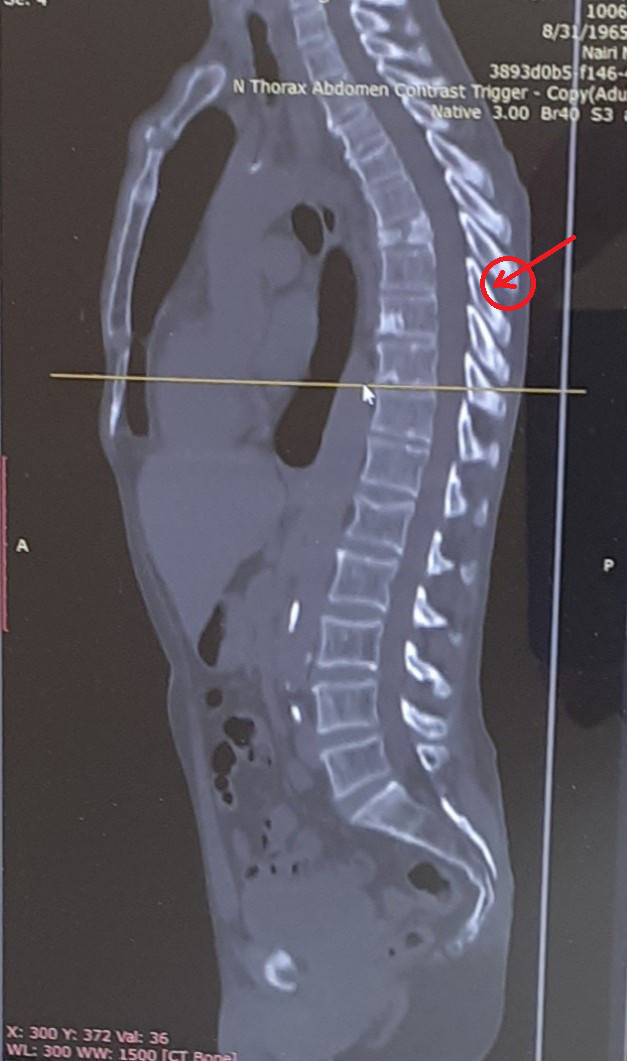

55 տարեկան տղամարդն Ուռուցքաբանության ազգային կենտրոն է ընդունվել կրծքային 7-րդ ողի ախտաբանական, այսինքն վնասվածքին ոչ բնորոշ մեխանիզմով ստացված կոտրվածքով, որն առաջացել էր ընդամենը 50կգ ծանրությամբ բեռ բարձրացնելու արդյունքում։ Ինչից ելնելով բժիշկները կասկածել են, որ կա ողերի մետաստատիկ ախտահարում։

Կատարված մագնիսառեզոնանսային և համակարգչային տոմոգրաֆիաների արդյունքում կասկածվել է շագանակագեղձի քաղցկեղ և մետաստազներ ողերում։ Սակայն ՈՒԱԿ-ում կատարված հետազոտությունները հերքել են նախնական վարկածը․ կատարվել է 7-րդ ողի տրեպան բիոպսիա և ուռուցքային ախտահարում չի հայտնաբերվել՝ ոչ առաջնային, ոչ էլ երկրորդային բնույթի։ Ինչից հետո որոշվել է կատարել վիրահատություն՝ ողնաշարի կայունացում։

«Քանի որ, ամեն դեպքում, հիվանդի մոտ կոտրվածքի այլ պատճառ չի հայտնաբերվել,  մեր մոտեցումը եղել է հետևյալը․ եթե լիներ քաղցկեղով հիվանդ, ի՞նչ կանեինք։ Հենց այդ մոտեցմամբ էլ մենք գնահատել ենք ողնաշարի անկայունությունը (ըստ SINS սանդղակի) և սպասվող կյանքի տևողությունը (Տոկոհուշիի վերանայված սանդղակով) ։ Եվ ուրոլոգների հետ համատեղ գնացել ենք վիրահատական միջամտության։ Մենք կատարել ենք կրծքային   5,6,8,9 ողերի տրանսպեդիկուլյար ֆիքսացիա՝ բազմաառանցքային տիտանե պտուտակներով։ Ուրոլոգները կատարել են շագանակագեղձի տրանսուրետրալ բիոպսիա, որի արդյունքում ստացվել է PIN1 և PIN2 (prostatic intraepithelial neoplasia), ինչը համարվում է նախաքաղցկեղային վիճակ և պահանջում է դինամիկ հսկողություն», - պատմեց Կարապետ Անտոնյանը։

Նա պարզաբանեց, որ բժիշկները ֆիքսել են 4 ող, ոչ թե 2, քանի որ  ՀՇ-ի վրա նկատելի էր փուշելունների հեռացում, ինչը նշանակում է, որ ողնաշարի հետին կայունացնող և տարածիչ կապանները վնասված են (ըստ AO SPINE դասակարգման B2 տիպի վնասվածք)։ «Մենք այդ վնասվածքը ինտրաօպերացիոն հայտնաբերել ենք, տեսել ենք, որ այն իսկապես կա, և համոզվել ենք, որ երկար հատվածի ֆիքսացիայի մեր որոշումը ճիշտ էր», - ասաց նա։